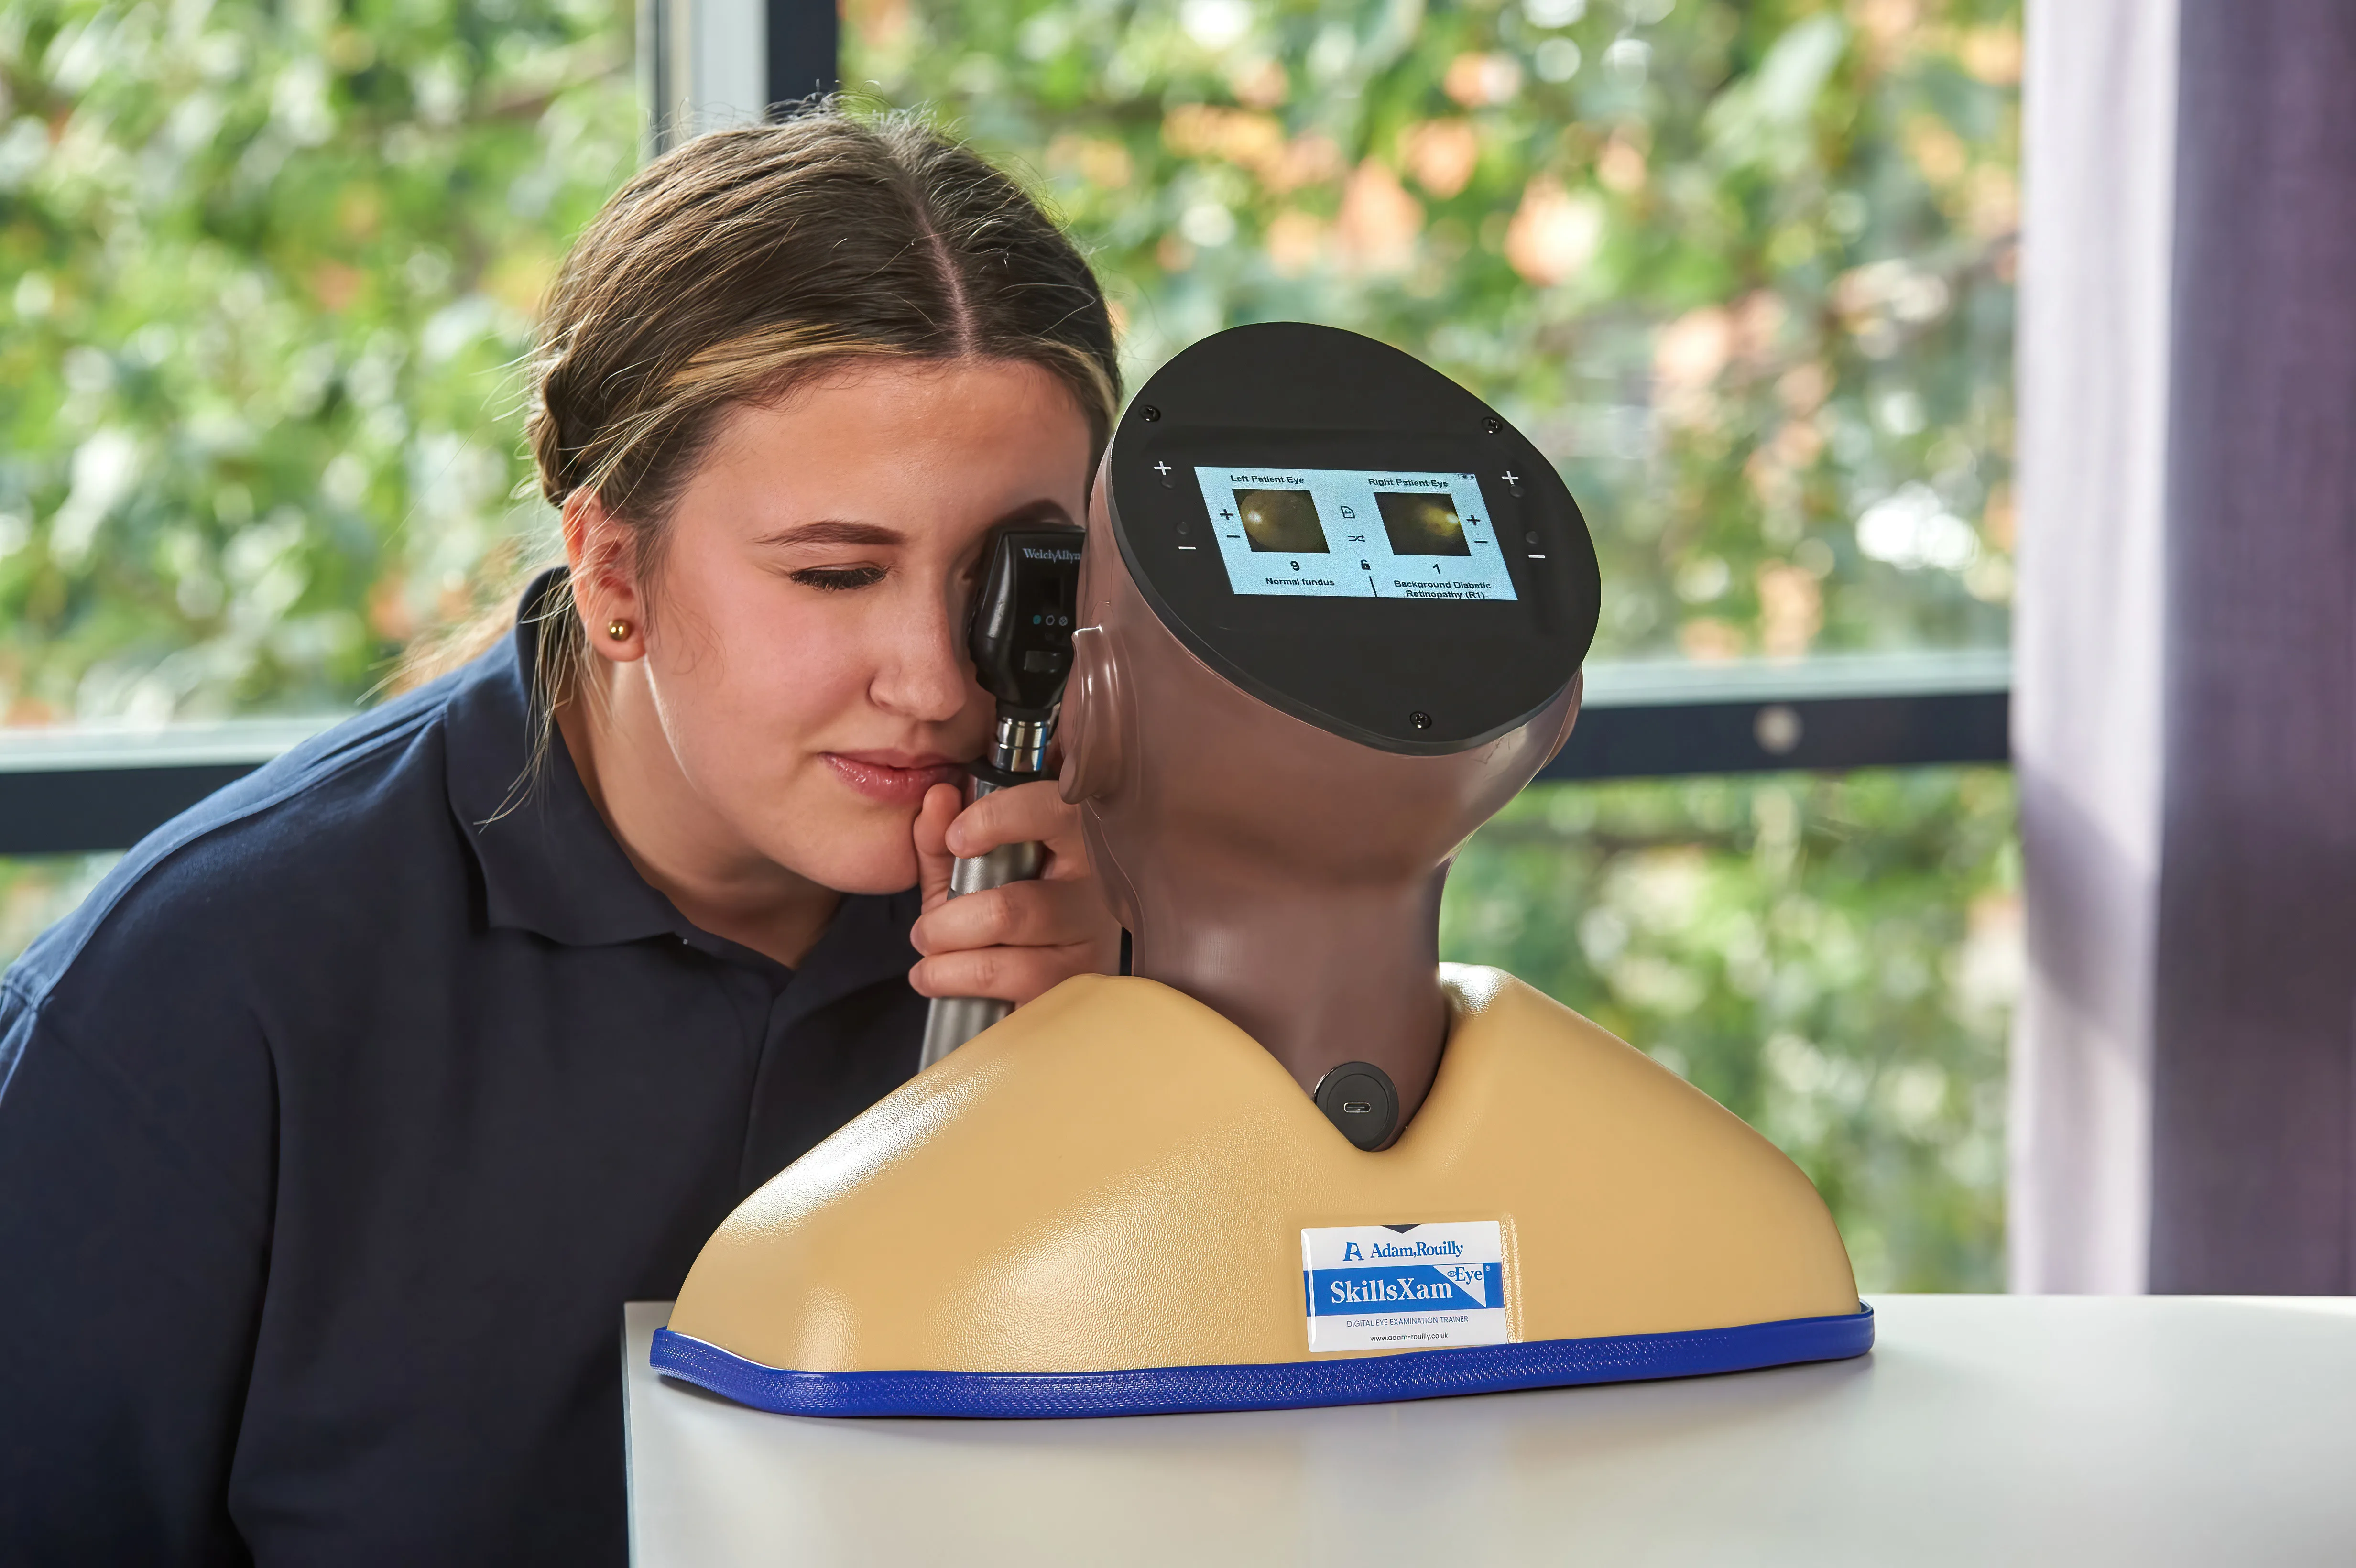

Developed in collaboration with Professor Vinod Patel, Professor, Diabetes and Clinical Skills, the Enhanced Digital Eye Examination Trainer takes ophthalmoscopy training to a new level of realism and inclusivity.

For the first time, advanced digital technology allows trainees to experience how the same eye condition can present differently in patients with light and dark skin tones. In darker-skinned patients, deeper pigmentation in the fundus reduces vessel visibility, a nuance replicated only in the AR503/50 Dark model. This provides learners with invaluable exposure to the clinical variations they will encounter in real practice, enhancing both competence and confidence. Offering two product versions enables trainees to gain an awareness of these visible variances.

Inside the model, conditions are displayed with greater clarity and true-to-life colour on high-resolution circular LCD screens. A 4.3-inch external touchscreen interface makes operation intuitive and effective, allowing users to preview, search, and select conditions or build customisable sets for teaching, self-directed learning, or examination scenarios.

The Enhanced Digital Eye Examination Trainer delivers an authentic, adaptive, and inclusive learning experience, redefining the standard in ophthalmoscopy training.